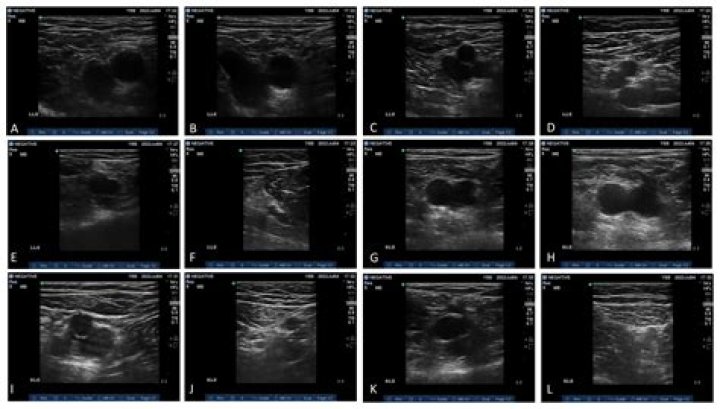

Can ultrasounds detect lumps?

Ultrasound imaging can help determine the composition of lump, distinguishing between a cyst and a tumour. Also known as sonography, it involves the use of high-frequency, real-time sound waves to create an image.